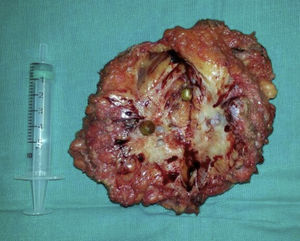

Seguidamente se realizan gastroscopia y colonoscopia que descartan malignidad. El CEA es normal y destaca un CA 19.9 elevado de 2000. Se realiza PET-TAC, no identificándose otras lesiones salvo la tumoración abdominal. Ante los hallazgos se decide intervención quirúrgica. Se realiza laparotomía media supra-infraumbilical. Se observa una tumoración umbilical de aspecto granulomatoso que contiene en su interior varias lesiones redondeadas que impresionan de cálculos biliares. La lesión contacta focalmente con el epiplón y se identifican implantes tumorales. Se realiza resección tumoral amplia, incluyendo epiplón y peritonectomía. Para el cierre de pared, se utilizaron varias suturas continuas con loop 1 monofilamento y no fue necesaria la colocación de malla, que también se desestimó por el riesgo de recidiva tumoral.

El informe anatomopatológico final confirma que se trata de un adenocarcinoma infiltrante pobremente diferenciado de predominio micropapilar (positivo para CK 7,20,19, CEA y CD X2) que sugiere tumor primario biliar extrahepático.